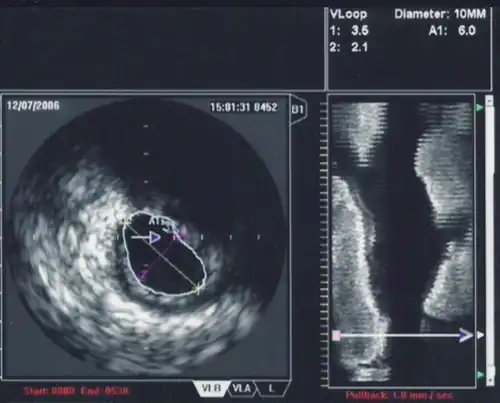

Intravascular ultrasound (IVUS) or intravascular echocardiography is a medical imaging methodology using a specially designed catheter with a miniaturized ultrasound probe attached to the distal end of the catheter. The proximal end of the catheter is attached to computerized ultrasound equipment. It allows the application of ultrasound technology, such as piezoelectric transducer or CMUT, to see from inside blood vessels out through the surrounding blood column, visualizing the endothelium (inner wall) of blood vessels.[1]

The ultrasound catheter tip is slid in over the guidewire and positioned, using angiography techniques so that the tip is at the farthest away position to be imaged. The sound waves are emitted from the catheter tip, are usually in the 20-40 MHz range, and the catheter also receives and conducts the return echo information out to the external computerized ultrasound equipment which constructs and displays a real time ultrasound image of a thin section of the blood vessel currently surrounding the catheter tip, usually displayed at 30 frames/second image.

The guide wire is kept stationary and the ultrasound catheter tip is slid backwards, usually under motorized control at a pullback speed of 0.5 mm/s. (The motorized pullback tends to be smoother than hand movement by the physician.)

The (a) blood vessel wall inner lining, (b) atheromatous disease within the wall and (c) connective tissues covering the outer surface of the blood vessel are echogenic, i.e. they return echoes making them visible on the ultrasound display.

By contrast, the blood itself and the healthy muscular tissue portion of the blood vessel wall is relatively echolucent, just black circular spaces, in the images.